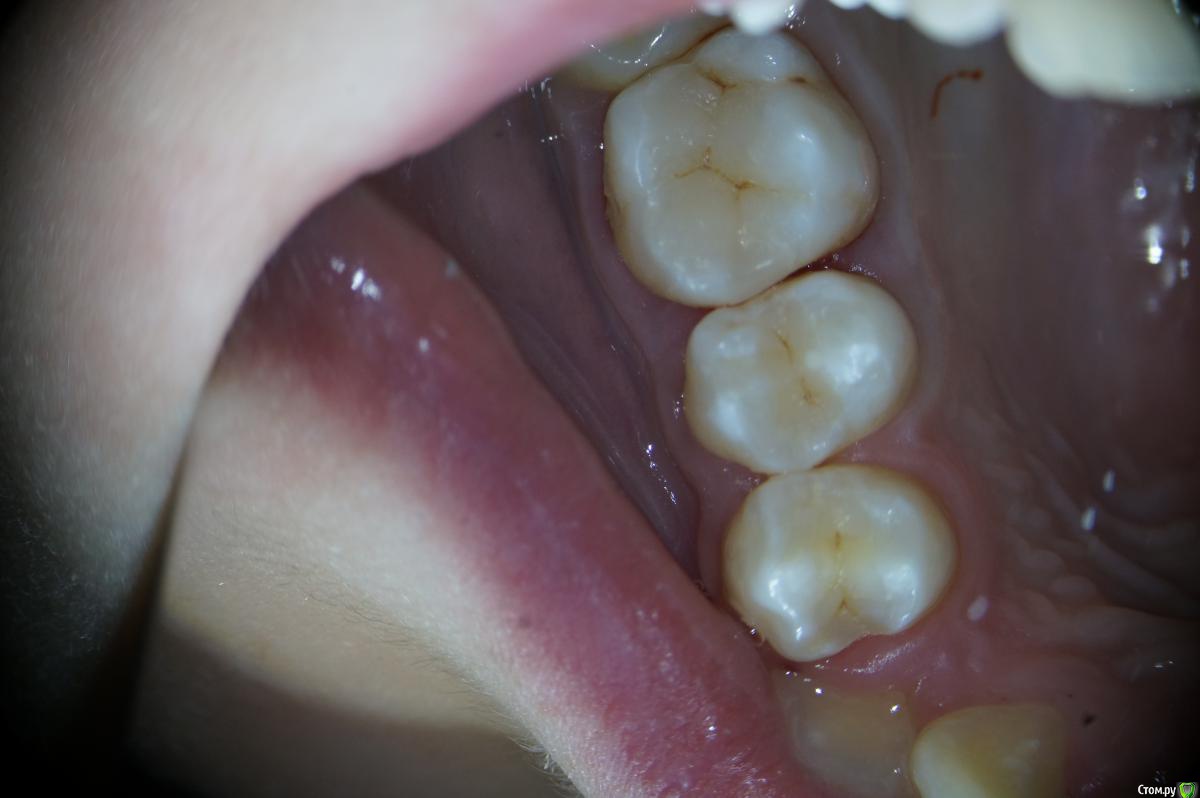

Hans85 Опубликовано 15 января, 2014 Автор Поделиться Опубликовано 15 января, 2014 Сразу скажу что с эндо у меня обстоит лучше чем с реставрациями так что сильно не пинайте.Пациентка страховая,так что речь про вкладки не идет.так сказать возможность тренится в художественной лепке.ЗУбы 26 25 24.На фото 26 уже сделанный. 7 Ссылка на комментарий

Hans85 Опубликовано 14 января, 2015 Автор Поделиться Опубликовано 14 января, 2015 для разбавления эндо чутка занимаюсь художественной лепкой,да Маэстро еще далеко,но будем учиться. 13 Ссылка на комментарий